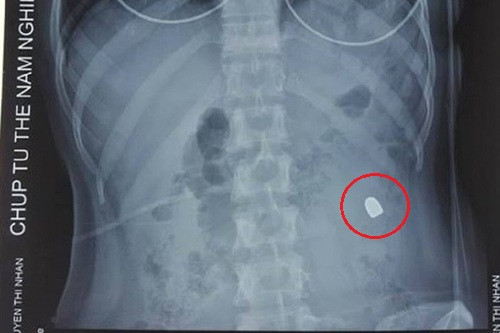

Vụ nổ súng khiến chị Nguyễn Thị Nhẫn (32 tuổi) đi xe máy ngang qua bị đạn trúng vùng bụng, chị Nguyễn Thị Thu Hương (32 tuổi) đang ngồi ăn tại quán ốc trước cửa quán karaoke bị thương tại thái dương.

Hình ảnh vết đạn găm vào chị Nhẫn.

Ngày 22/11, chị Nhẫn vẫn phải điều trị ở Bệnh viện E (Hà Nội). Sau cuộc phẫu thuật nhiều giờ, chị đã qua cơn nguy kịch song hiện vẫn nằm liệt giường. Mẹ chị cho hay tối 20/11, Nhẫn trúng đạn khi đang ở gần nhà. Một người dân đã giúp đỡ đưa về. "Nhẫn chỉ kêu đau ở bụng rồi ngất xỉu. Phát hiện máu chảy, gia đình tôi vội đưa con đi cấp cứu. Nhẫn phải cắt bỏ một phần ruột già do đạn găm sâu”, bà nói.